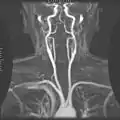

Слуховая труба. Разрез по длинной оси. Магнитно-резонансная ангиография.

Магнитно-резонансная ангиография.- Внутренняя сонная артерия.